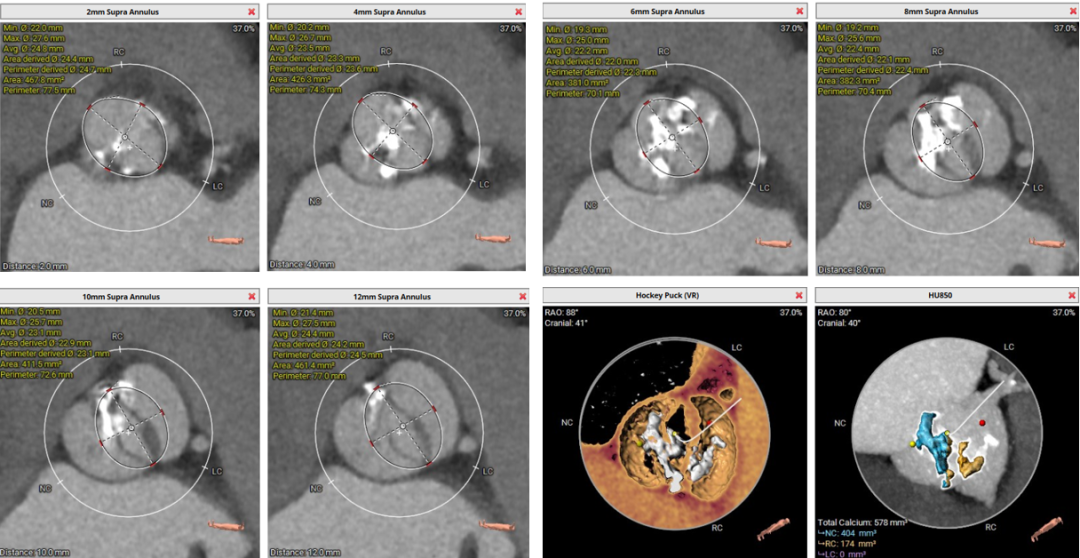

术前CT评估

• 先天二叶式主动脉瓣,瓣环径为23.7mm,瓣叶增厚伴重度钙化,钙化分布不均,主要分布于两窦交界处一侧;

• 冠脉开口高度可,切线角度测量未见冗长瓣叶;

• 瓦氏窦、窦管交界内径尚可,升主动脉扩张;

• 左室腔内径正常,心室壁增厚;

• 瓣环水平夹角为52°,主动脉弓宽度、角度尚可;

主动脉根部测量

瓣上结构测量

冠脉阻挡风险及左室大小评估